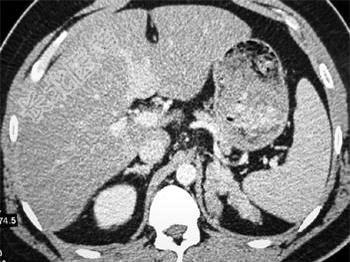

- 单项选择题男性,27岁, 侏儒,因脱水曾在数家医院住过院, 结合所示图像,最可能的诊断是 ( )

A、先天性肾上腺增生肥大

B、库欣综合征

C、肾上腺癌

D、腺瘤状增生肥大

E、嗜铬细胞瘤